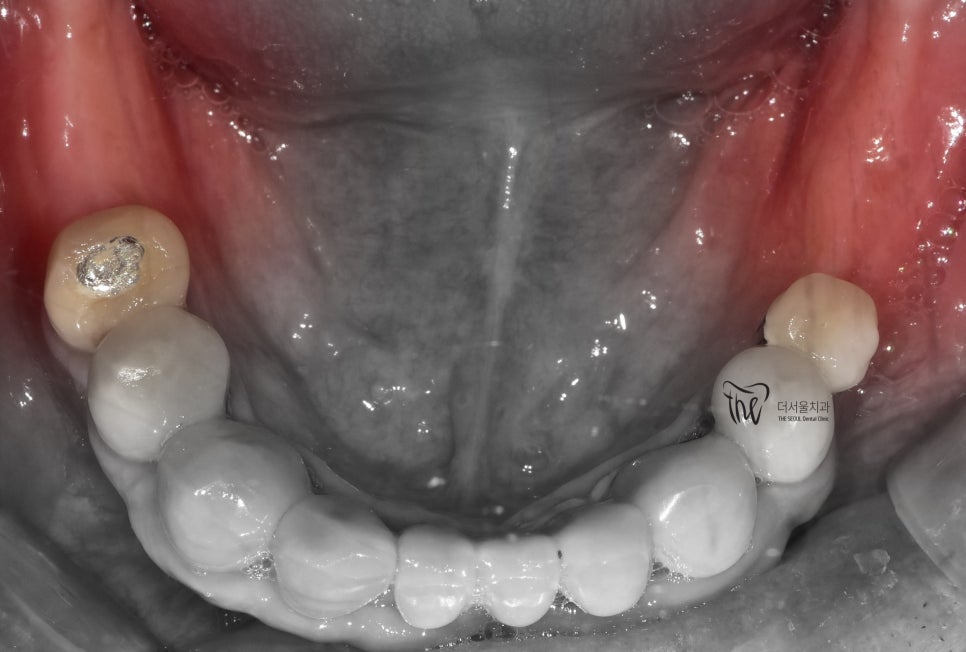

엑스레이를 보면, 아래턱에 어금니들이

결손이 되어있는 것을 볼 수 있습니다.

여튼 위, 엑스레이를 보면서 하나씩 설명드릴게요

1) 이분은, 구강 내 전체적으로 치주염을 앓고

계셨으며 치석 또한 곳곳에 많이 쌓여있었습니다.

따라서, 치조골이 많이 위축 됨에 따라서 하방으로

이동되어 치아의 뿌리가 겉으로 다 드러나

있는 것을 볼 수 있습니다.

다만, 브릿지 보철로 연결이 되어있기 때문에

치아 정출에 관련되어서는 크게 신경 쓸 것은

아니나 추후에는 치료를 반드시 꼭 해야 되는 상황.

2) 1번내용과는 다르게,

상악 어금니만 남아있으며

아래에는 어금니들이 없습니다.

즉, 교합관계를

형성하지 않고 있기 때문에

교합 기능을 전혀 이룰 수 없는 상태입니다.

아울러, 윗니들은 아랫니들이 없기 때문에

점차 아래로 내려오는 ‘치아 정출’ 현상이

지속적으로 나타나면서 추후에 쉽게 발치로

이어지게 되는 상황이 우려됩니다.